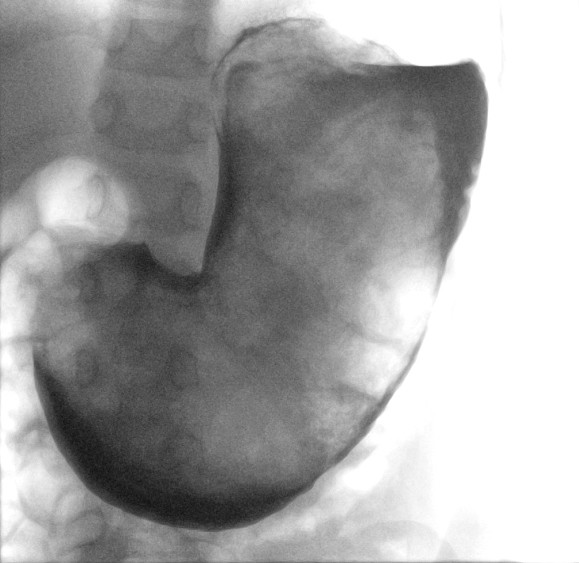

Ved undersøkelse var pasientens allmenntilstand god, men det var en hard oppfylling på ca. 20 cm i diameter fra epigastriet ned til under navlenivå. Blodprøvene viste hemoglobin 10,5 g/dl (referanseområde 11,0–15,5) og alaninaminotransferase (ALAT) 49 U/L (10–45). Øvrige lever- og galleprøver samt CRP- og leukocyttverdier var normale. Ultralydundersøkelse av abdomen påviste en oppfylling på magesekkens plass. Denne var også synlig på røntgen oversikt abdomen. Supplerende røntgenkontrastundersøkelse fremstilte en oppfylling som inntok hele magesekken, forenlig med en «svært stor besoar» (figur 1). På bakgrunn av opplysningene om tidligere trikotillofagi antok man at det dreide seg om en trikobesoar.

Trikobesoarer kan nå betydelig størrelse før de gir symptomer som beskrevet i denne kasuistikken der hele magesekken var utfylt av besoaren (figur 1). Videre preoperative undersøkelser var ikke nødvendig. CT-undersøkelse med kontrast er rapportert å kunne diagnostisere 97 % av besoarer i magesekken (7), men representerer en betydelig strålebelastning, som det var mulig å unngå hos dette barnet.